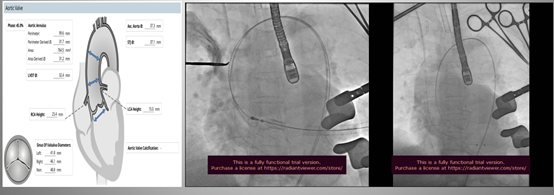

82岁女性,重度主动脉瓣狭窄伴冠心病(一站式)